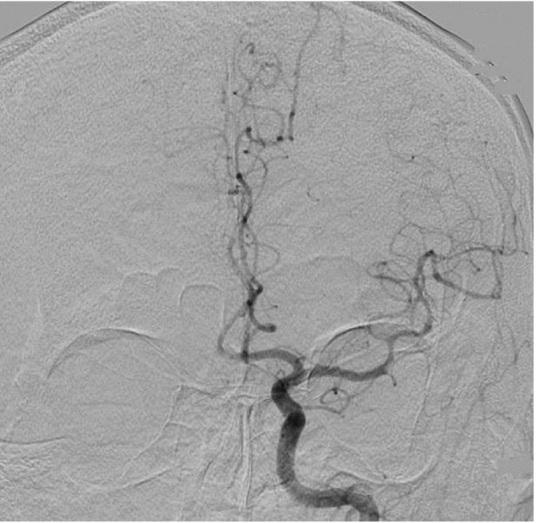

The optional endovascular approach for acute ischemic stroke is unclear. The Trevo stent retriever can be used as first-line treatment for fast mechanical recanalization. The authors developed a treatment protocol for acute ischemic stroke based on the assessment of clot quality during clot removal with the Trevo. This prospective single-center study included all patients admitted for acute ischemic stroke between July 2014 and February 2015, who underwent emergency endovascular treatment. According to the protocol, the Trevo was used for first-line treatment. Immediately after the Trevo was deployed, the stent delivery wire was pushed to open the stent by force (ACAPT technique). Clot quality was assessed on the basis of the perfusion status after deployment of the Trevo; continued occlusion or immediate reopening either reoccluded or maintained after the stent retriever had been in place for 5 min. If there was no obvious clot removal after the first pass with the Trevo, according to the quality of the clot, either a second pass was performed or another endovascular device was selected. Twelve consecutive patients with acute major cerebral artery occlusion were analyzed. Thrombolysis in cerebral infarction score 2b and 3 was achieved in 11 patients (91.7%) and 9 (75%) had a good clinical outcome after 90 days based on a modified Rankin scale score ≤ 2. Symptomatic intracranial hemorrhage occurred in 1 patient (8.3%). The overall mortality rate was 8.3%. Endovascular thrombectomy using the Trevo stent retriever for first-line treatment is feasible and effective.

急性缺血性卒中的选择性血管内治疗方法尚不清楚。Trevo支架取栓器可作为快速机械再通的一线治疗方法。作者基于使用Trevo取栓过程中对血栓质量的评估,制定了一种急性缺血性卒中的治疗方案。这项前瞻性单中心研究纳入了2014年7月至2015年2月期间因急性缺血性卒中入院并接受急诊血管内治疗的所有患者。根据该方案,Trevo被用作一线治疗。在部署Trevo后,立即用力推送支架输送钢丝以打开支架(ACAPT技术)。根据Trevo部署后的灌注状态评估血栓质量;持续闭塞或立即再通,在支架取栓器放置5分钟后要么再次闭塞要么保持通畅。如果使用Trevo首次取栓后没有明显的血栓清除,根据血栓质量,要么进行第二次取栓,要么选择另一种血管内装置。对连续12例急性大脑中动脉闭塞患者进行了分析。11例患者(91.7%)达到脑梗死溶栓评分2b和3分,90天后基于改良Rankin量表评分≤2,9例(75%)患者获得良好的临床结局。1例患者(8.3%)发生有症状性颅内出血。总死亡率为8.3%。使用Trevo支架取栓器进行一线治疗的血管内血栓切除术是可行且有效的。